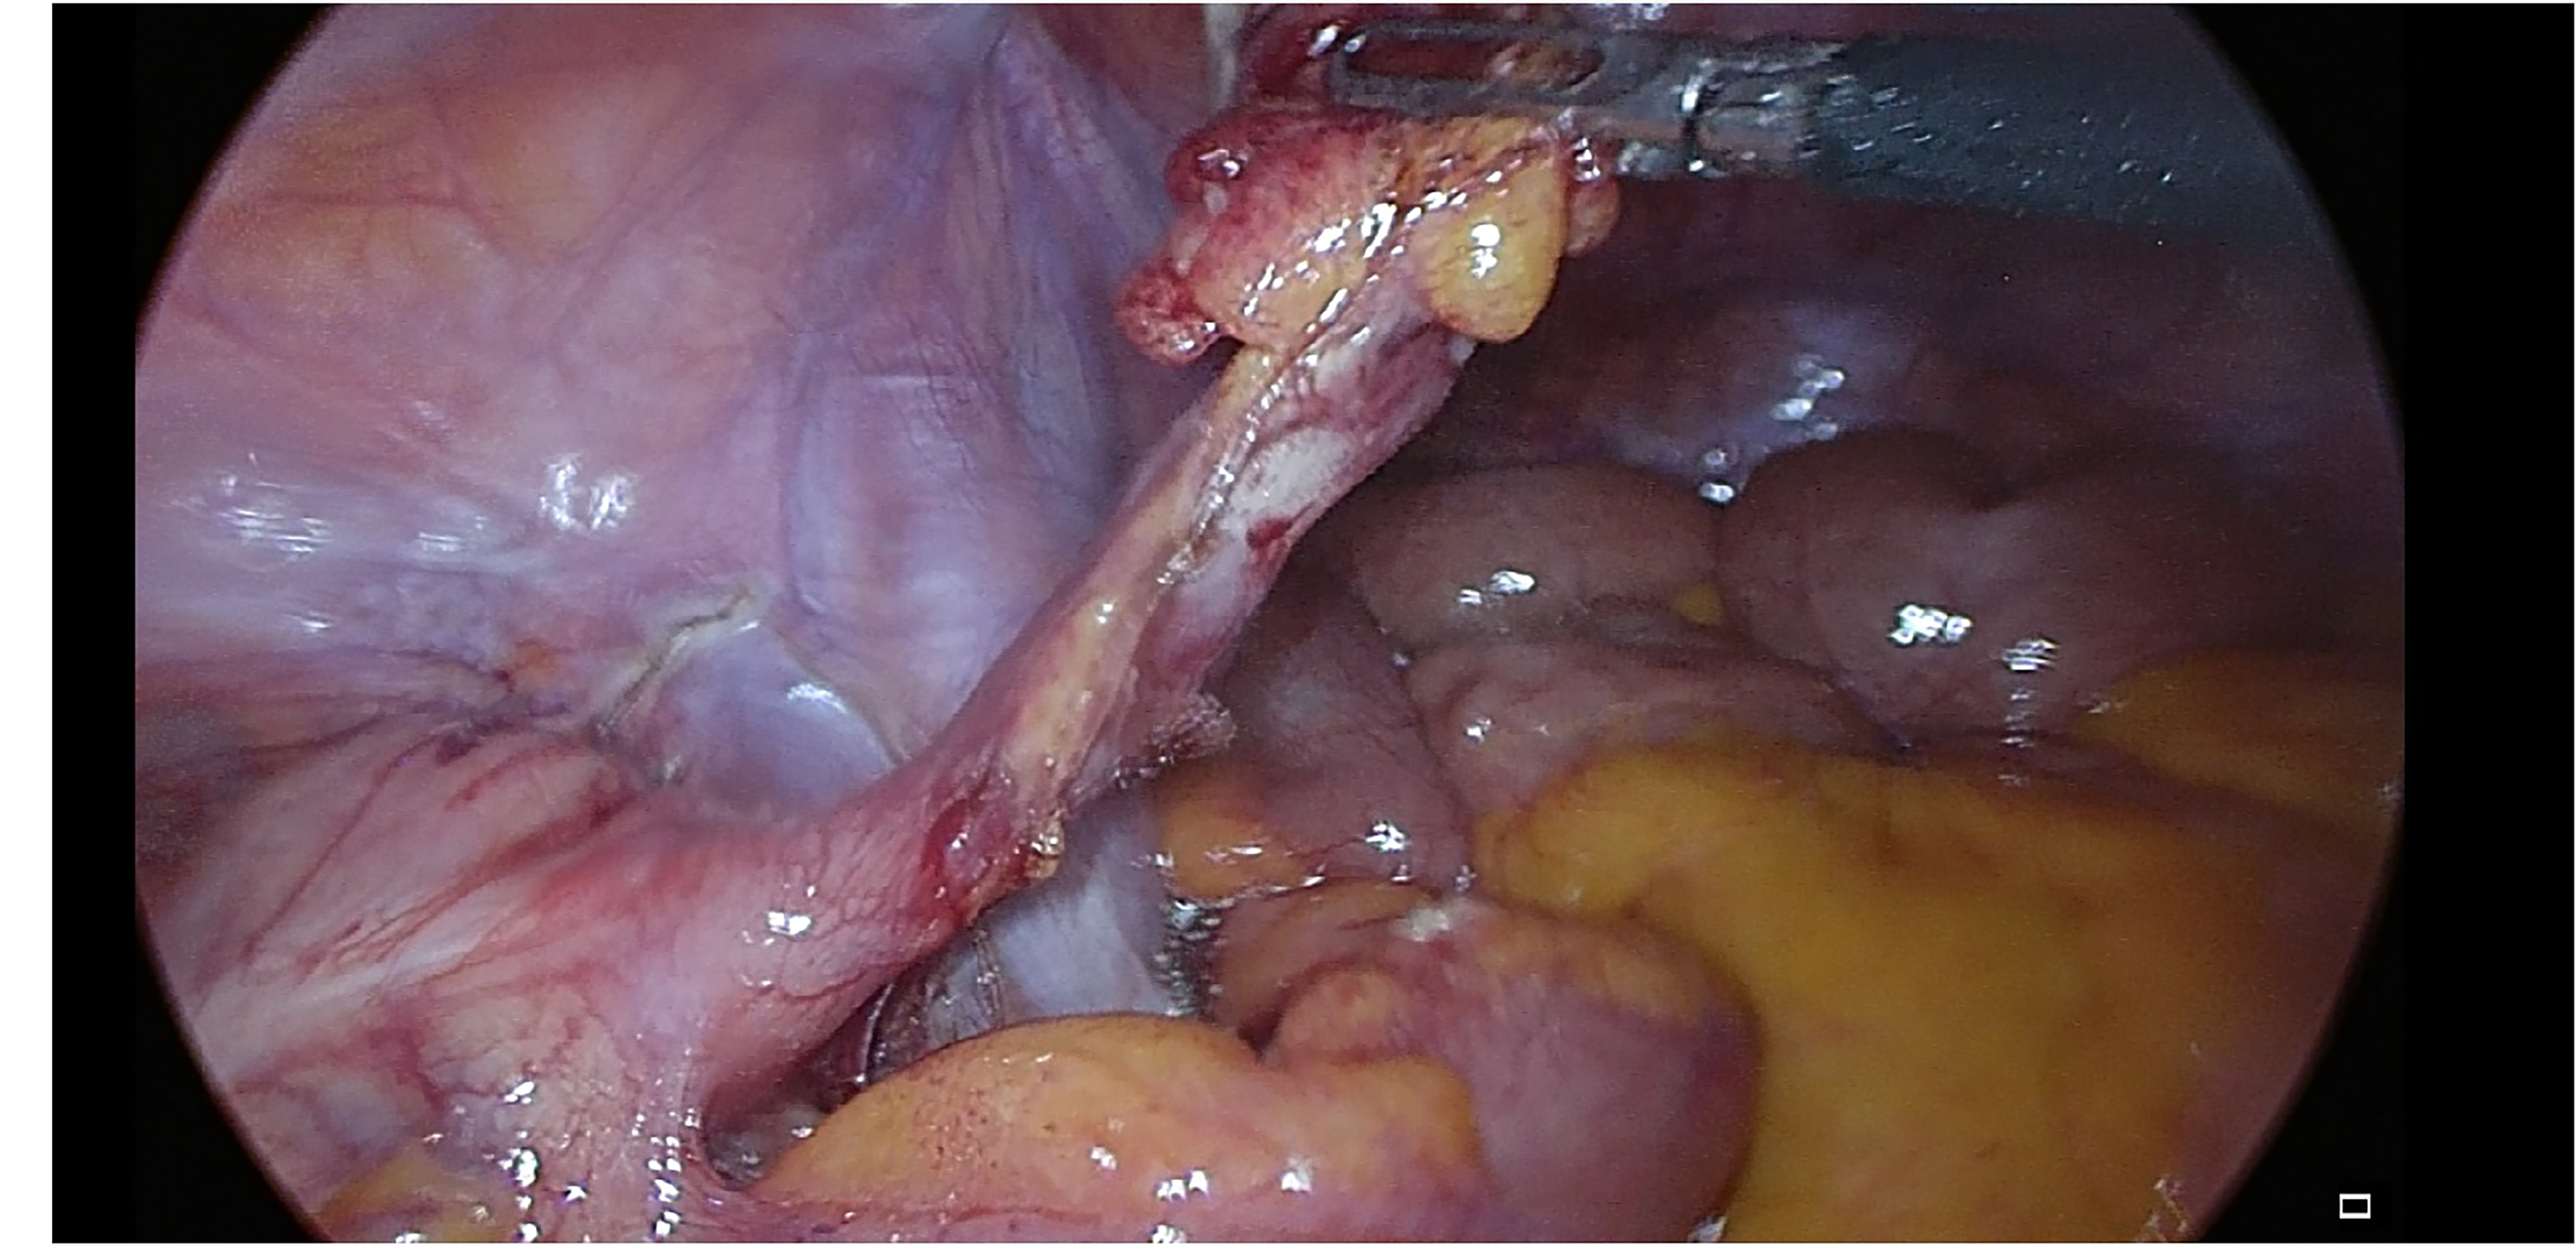

The appendectomy approach in patients with situs inversus is performed with the same technique as the appendicitis approach in the normal position. Laparoscopic or open methods can be applied, as in our case. Laparoscopic appendectomy was performed for the first time by Contini in 1998 in the case of totalis with situs inversus. It is also available in the literature that trocars can be placed differently.7 In our clinic, we routinely perform laparoscopic appendectomy with three ports. Since our patient had situs inversus totalis, we entered the port, which we normally enter from the left lower quadrant and the right lower quadrant. Other ports were entered at their normal places (Figure 1).

Figure 1

Figure 1. Intraoperative view of the appendix